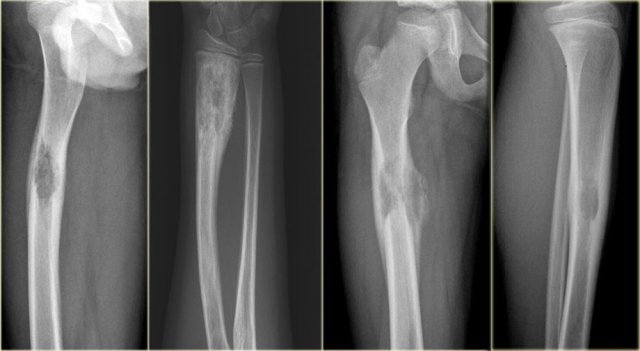

On the left a patient with a Ewing's sarcoma in the femur.

Notice the ill-defined osteolysis.

There is an aggressive periosteal reaction.

On the left an ill-defined lytic lesion in the femur of a young patient.

There is a permeative destruction pattern with irregular cortical destruction.

There is an aggressive periosteal reaction (arrow).

This is also called sunburst appearance.